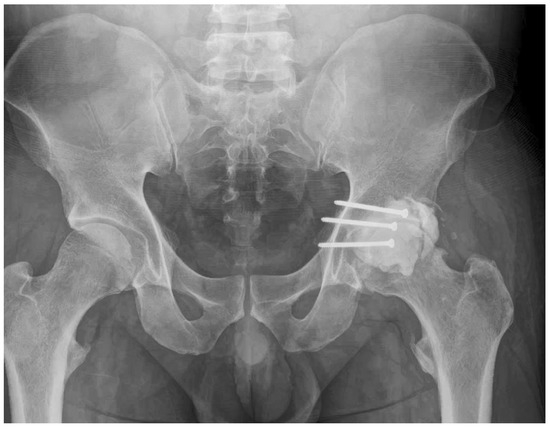

- Reduction and Final Assessment: The hip was reduced under direct vision. Intraoperative fluoroscopy confirmed a concentric reduction, correct implant placement, and the absence of cement fragments in the joint. The stability of the construct was tested through a range of motion. Postoperative imaging confirmed the anatomical reduction and the accurate contouring of the cement construct (Figure 4 and Figure 5).

- 3 Months: Radiographs showed a stable hip construct with no signs of subluxation or screw migration (Figure 7). The patient had returned to activities of daily living without major discomfort. The mHHS was 78/100.